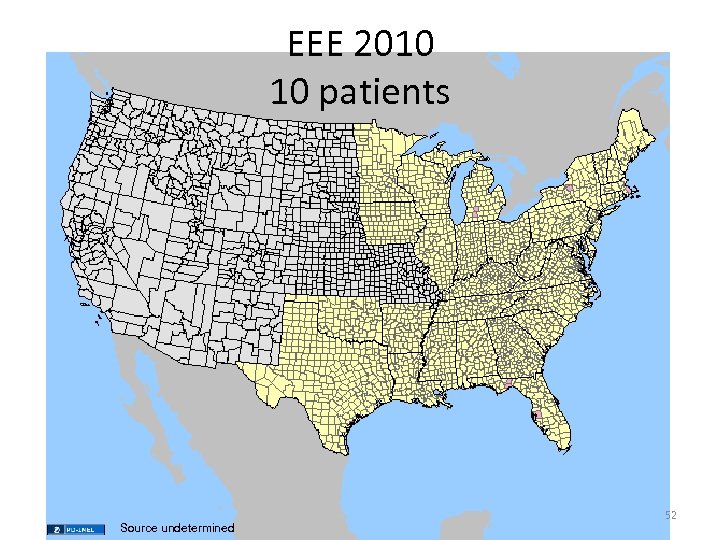

EEE 2010 10 patients Source undetermined 52